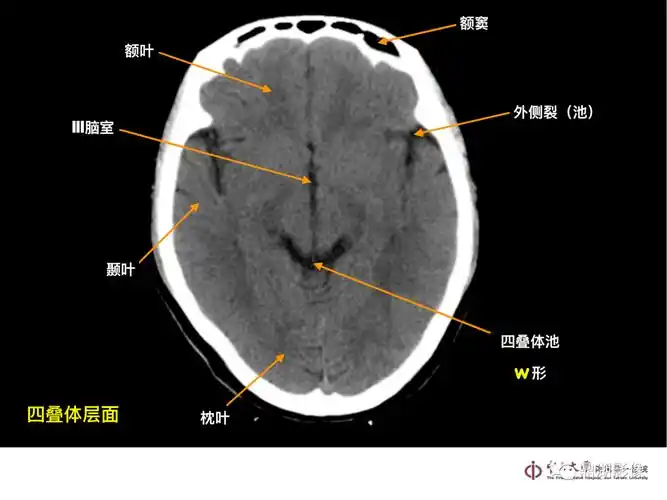

超实用!急诊头颅ct-"3b"阅片法